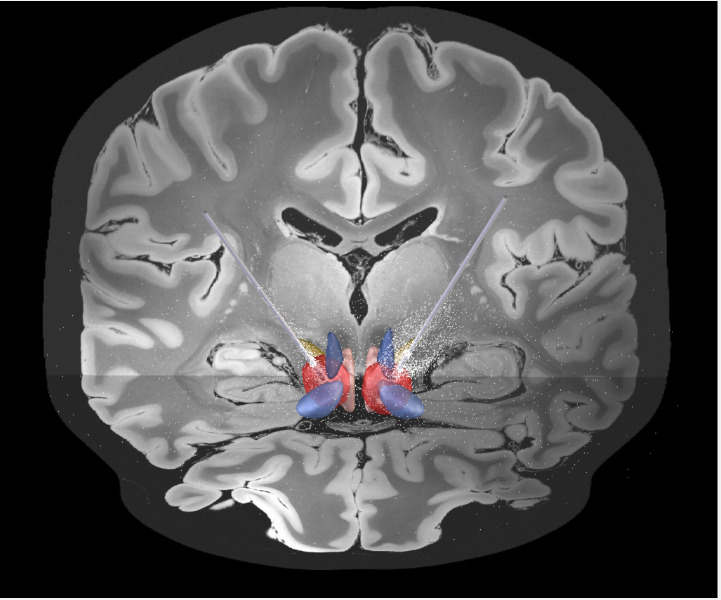

Brain stimulation can treat severe OCD. The results of Australian-first clinical trials featured on

@triplejHack.@QldBrainInst@QIMRBerghofer@DrPhilipMosley Listen from 20:40.#UQResearch https://www.abc.net.au/triplej/programs/hack/hack/13368384 …pic.twitter.com/Oc5k1Yzmji